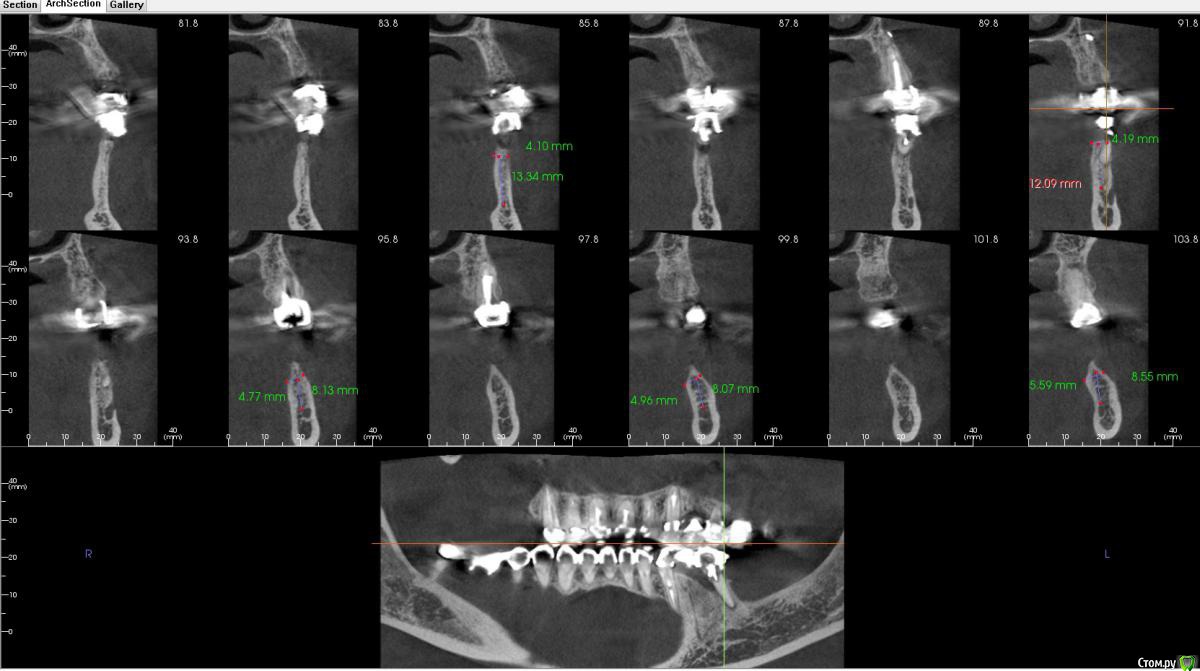

kamranchick Опубликовано 31 октября, 2018 Автор Поделиться Опубликовано 31 октября, 2018 Шаг 2 мм... Ссылка на комментарий

Bier Опубликовано 2 ноября, 2018 Поделиться Опубликовано 2 ноября, 2018 я честно говоря не понял в каком месте среза сколько кости. Где-то кости достаточно для установки имплантата без пластики, где-то нет. Ссылка на комментарий

kamranchick Опубликовано 3 ноября, 2018 Автор Поделиться Опубликовано 3 ноября, 2018 вот еще такие реформаты Ссылка на комментарий

Bier Опубликовано 3 ноября, 2018 Поделиться Опубликовано 3 ноября, 2018 блин, Камранчик, я вообще не понимаю в какую зону ты хочешь ставить и как твою нарезку прикрепить к панораме, которая ниже. Никакой системы координат нет.Короче там, где гребень 4.7 - можно крутить и не делать пластик. Ссылка на комментарий